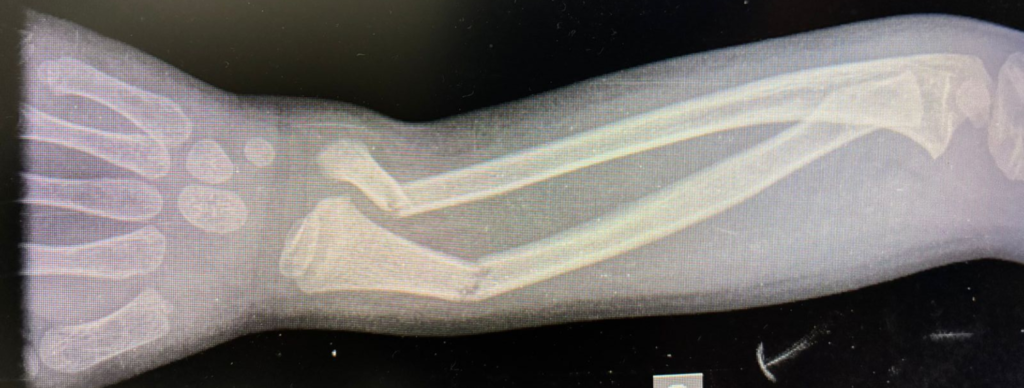

Fratura frisária